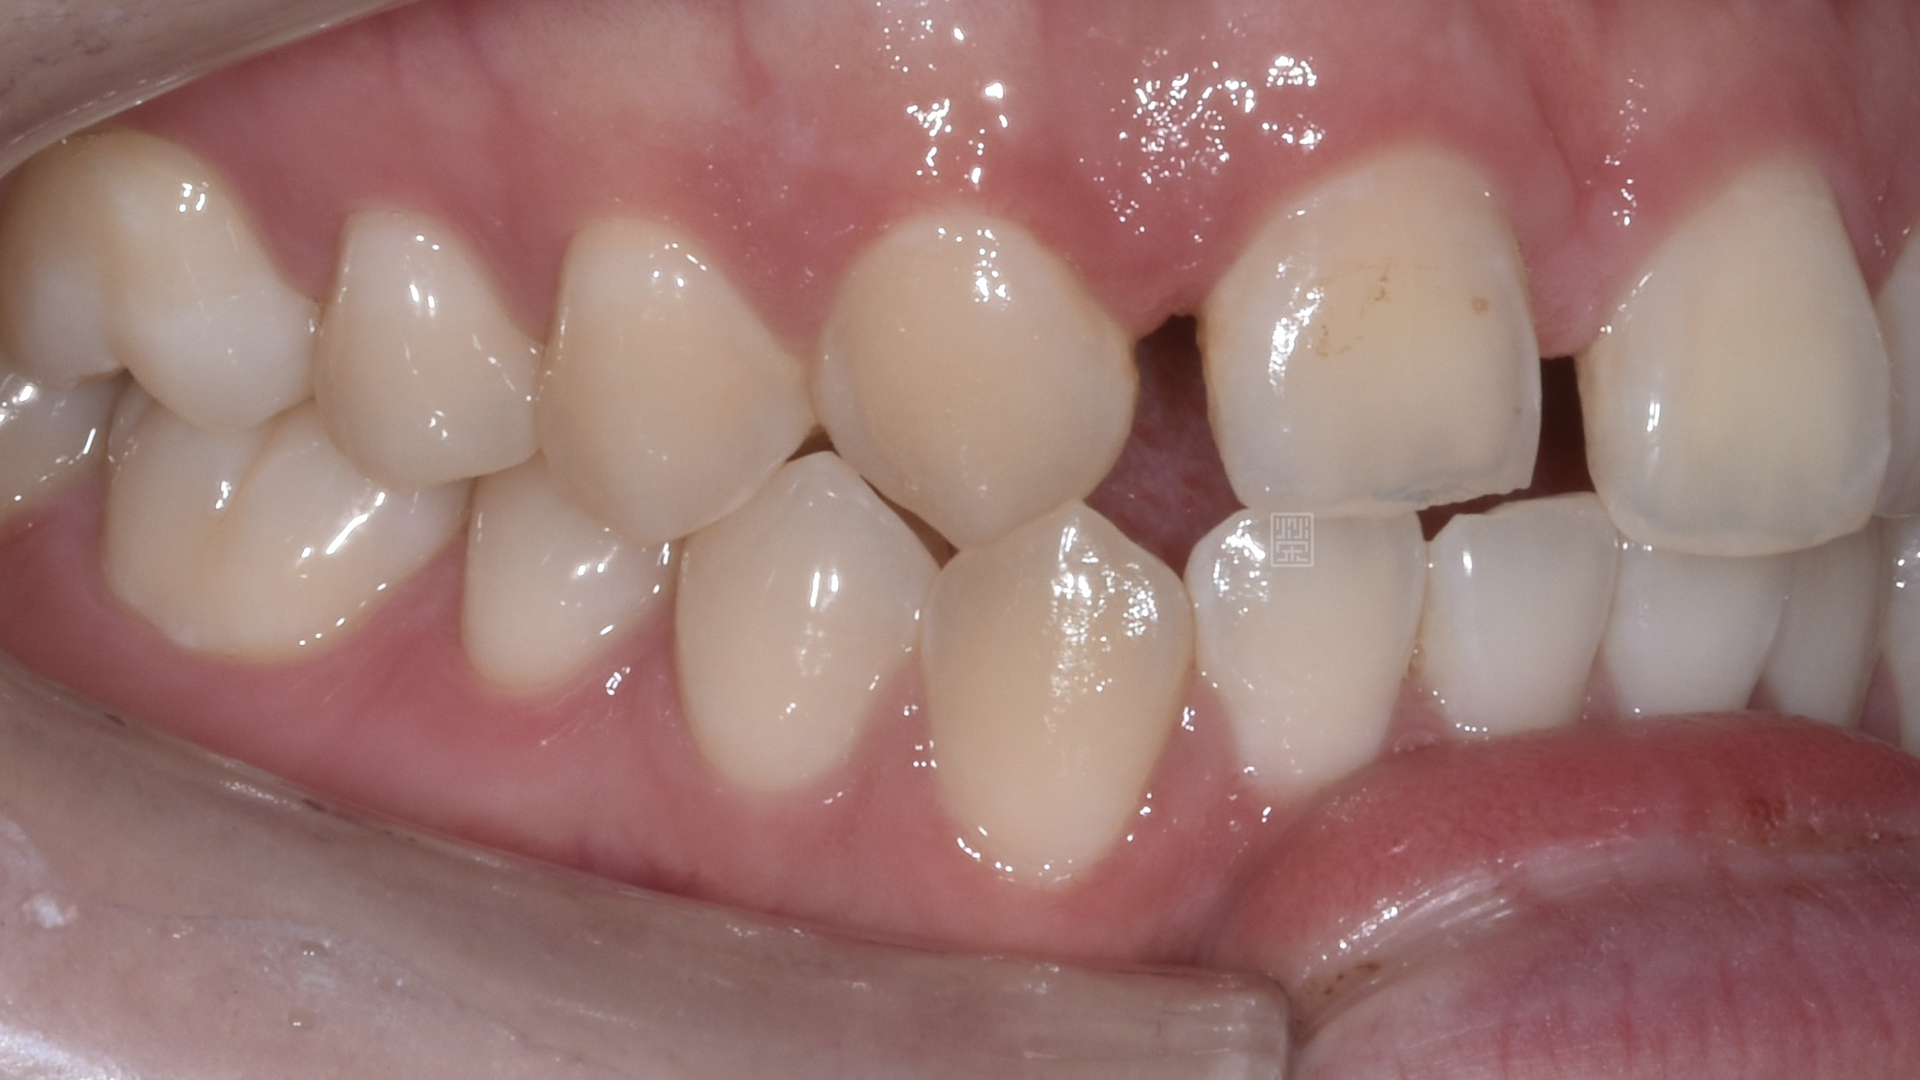

長期缺牙側門牙空間不足

治療前牙齒因車禍有縫且缺牙

姚小姐在國中時因為車禍外傷,造成右側門牙位置撞偏,右側側門牙撞飛,之前也想過處理,諮詢過許多醫師,不是覺得太複雜,就是建議直接牙齒拔除都用植牙來處理。